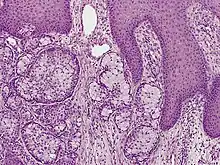

| Eccrine carcinoma, alveolar type | |

Eccrine carcinoma is a rare skin condition characterized by a plaque or nodule on the scalp, trunk, or extremities.[1]: 669 It originates from the eccrine sweat glands of the skin, accounting for less than 0.01% of diagnosed cutaneous malignancies.[2] Eccrine carcinoma tumors are locally aggressive, with a high rate of recurrence. Lack of reliable immunohistochemical markers and similarity to other common tumors has made identification of eccrine carcinoma difficult.[2]

Eccrine carcinomas include porocarcinoma, hidradenocarcinoma, malignant spiradenoma carcinoma, malignant cylindroma, syringoid eccrine carcinoma, microcystic adnexal carcinoma, mucinous carcinoma, adenoid cystic carcinoma, and ductal papillary adenocarcinoma.[2] Other tumors not classified include eccrine ductal carcinoma, basaloid eccrine carcinoma, clear cell eccrine carcinoma and non-specified sweat gland carcinomas.[2]